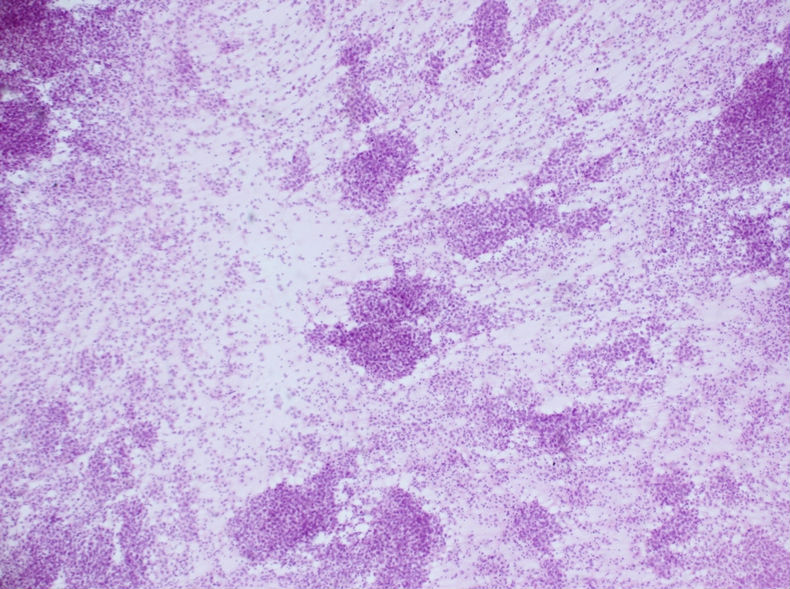

男性,30岁,左腹股沟淋巴结穿刺

男性,30岁,左腹股沟淋巴结穿刺图1

淋巴结转移性精原细胞瘤

我们的最终诊断就是淋巴结转移性精原细胞瘤,建议检查睾丸。

最后睾丸发现肿块,切除后组织学证实是精原细胞瘤

在这里病例中我们发现下拨成巢及散在排列,细胞异形,而且核仁明显。我想诊断恶性肿瘤没有任何疑议。

1、首先考虑byq想到的精原细胞瘤,男性患者,腹股沟淋巴肿大,细胞异形,核仁明显,的确要首先考虑到。

2、恶性黑色素瘤:这个部位,这样的细胞形态,恶黑与精原细胞瘤一样,是重点考虑对象,我没法区分两者应该谁考虑在前头。